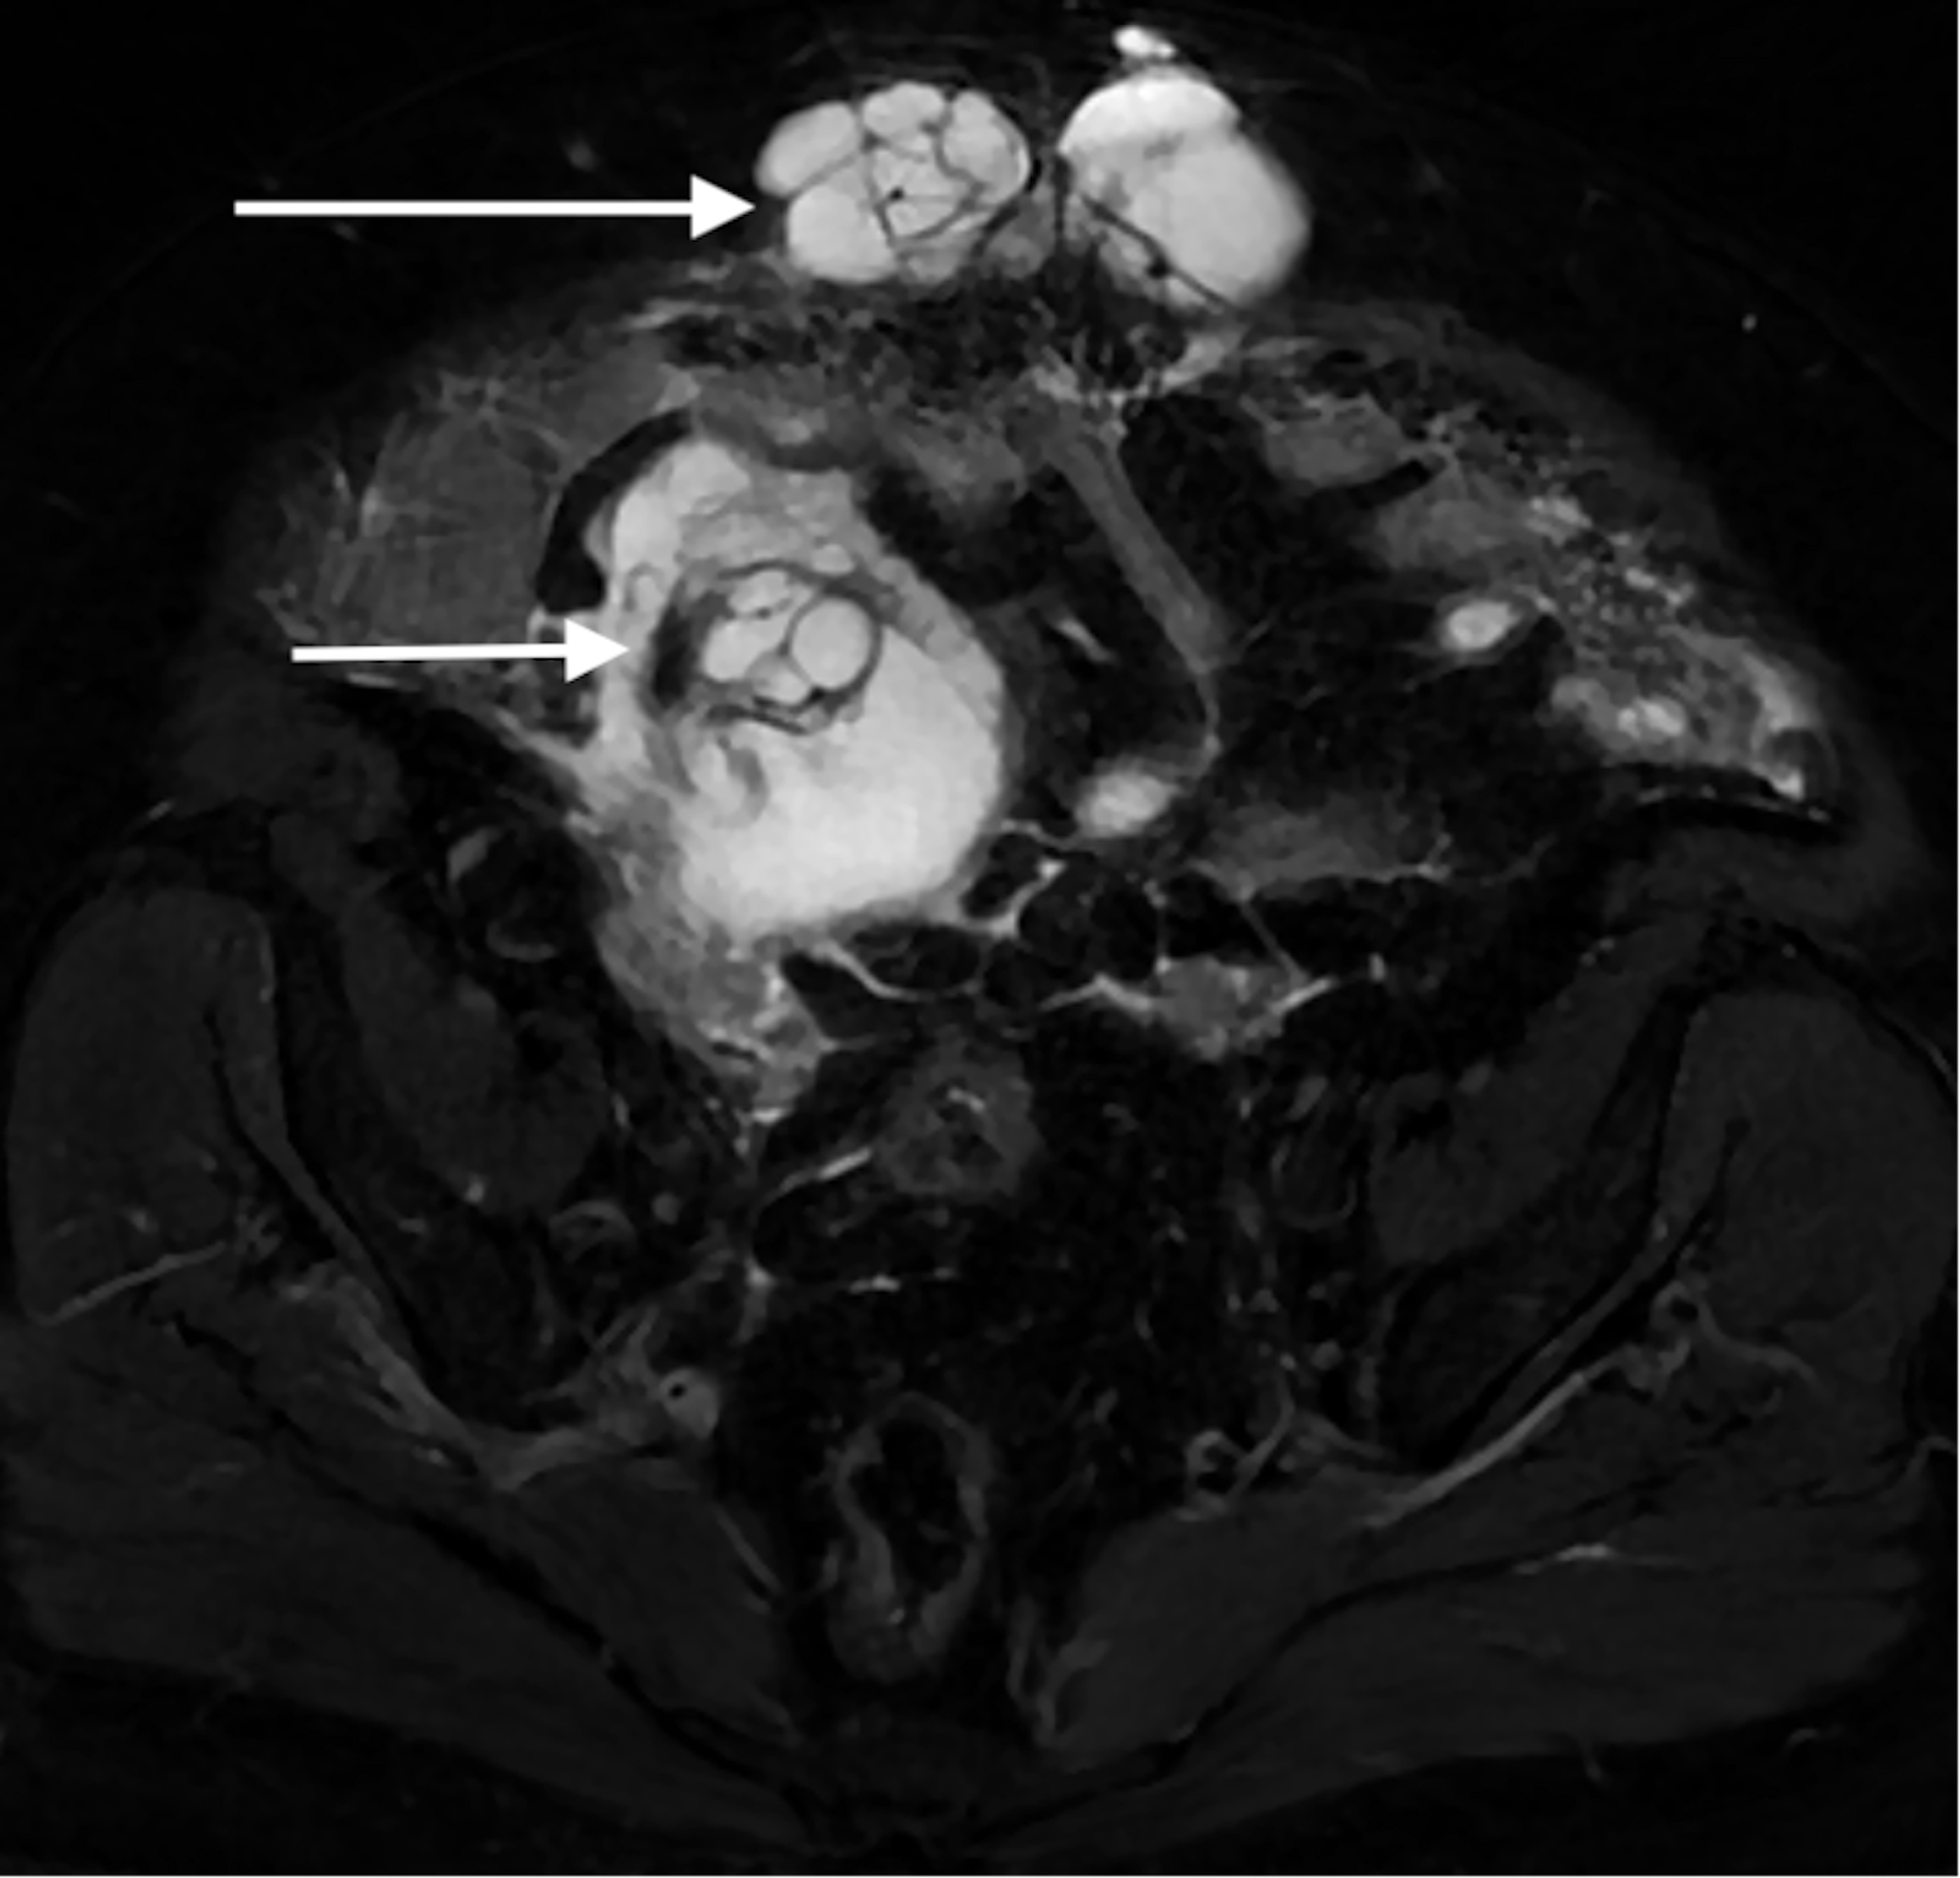

From www.cureus.com

Ruptured Appendiceal Mucocele Presenting as a Ventral Hernia A Case Ruptured Ventral Hernia Hernias can develop in several. Symptoms of a strangulated hernia include. In a strangulated ventral hernia, intestinal tissue gets tightly caught within an opening in your abdominal wall. A ventral hernia is the bulging of abdominal contents through the front of the abdominal wall. A hole or weakness in the. Umbilical and incisional hernias are specific types of. A ventral. Ruptured Ventral Hernia.

From www.researchgate.net

(PDF) Ruptured Appendiceal Mucocele Presenting as a Ventral Hernia A Ruptured Ventral Hernia A ventral (abdominal) hernia refers to any protrusion of intestine or other tissue through a weakness or gap in the abdominal wall. A ventral hernia, also known as an abdominal hernia, occurs when tissue protrudes through the abdomen wall due to a gap or weakness. Umbilical and incisional hernias are specific types of. Symptoms of a strangulated hernia include. A. Ruptured Ventral Hernia.

Cureus Ruptured Appendiceal Mucocele Presenting as a Ventral Hernia Ruptured Ventral Hernia Ventral hernias occur in the anterior abdominal wall and include primary ventral hernias (eg, epigastric, umbilical, spigelian,. Symptoms of a strangulated hernia include. A hole or weakness in the. Umbilical and incisional hernias are specific types of. Hernias can develop in several. A strangulated hernia is a hernia that is cutting off the blood supply to the intestines and tissues. Ruptured Ventral Hernia.